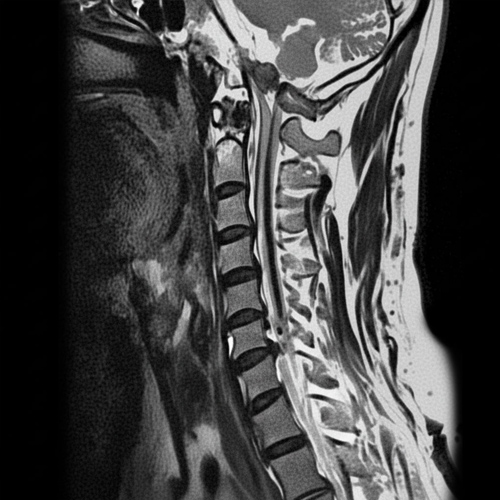

경추협착증

경추협착증은 경추(목 , 척추)의 척추관이 좁아져서 척추 신경이나 척수에 압박이 가해지는 상태를 말합니다.

경추(목뼈) 부의 척추관 협착증을 일컫는 말로 척추관이 좁아져 팔이나 다리로 가는 신경을 압박함으로써 증상이 나타나는 질환

신경의-눌림이-사라진-상태